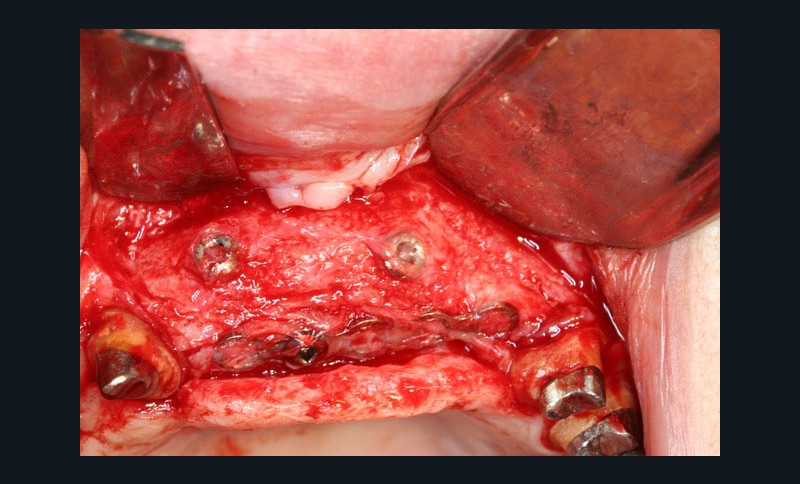

Dans la seconde partie de la soirée, le Docteur Surmenian, qui a intégré ces principes biologiques à ses protocoles d’augmentation osseuse, a pu développer ses nouvelles propositions thérapeutiques et leur apport comparativement aux procédures conventionnelles. Sa présentation, dont le titre interroge nos habitudes énonce l’ambition du concept chirurgical : « Faut-il tout changer pour simplifier et fiabiliser les augmentations osseuses ? » En convenant que les augmentations tridimensionnelles de la région postérieure mandibulaire constituent un défi thérapeutique que les techniques de greffes osseuses autologues en coffrage permettent de relever, le conférencier a rappelé à l’assistance toutes les difficultés associées à cette procédure. L’approche moins invasive suivie repose sur le choix de techniques de régénérations osseuses au moyen de particules cortico-spongieuses allogéniques et en respectant les fondamentaux biologiques tissulaires développés en première partie de soirée. Le recours à une plaque d’ostéosynthèse (Fast system®) maintenue à distance du site grâce à un ingénieux filetage résidant à la tête des vis de fixation offre une structure aisée à installer sur la crête à augmenter. Le dispositif rigide facilement stabilisé préserve le matériau venant combler l’espace du défaut, des pressions et tensions sus-jacentes. Le comblement est assuré à l’aide de particules cortico-spongieuses d’os allogène amalgamées à du PRF qui leur confèrent une consistance compacte (sticky bone).

La troisième approche consiste à libérer les lambeaux afin d’obtenir la laxité nécessaire à une fermeture sécurisée du site augmenté. Le relâchement du lambeau lingual décollé jusqu’à la ligne oblique interne est obtenu par un « brossage » apico-coronal de sa face interne à l’aide d’instruments spécifiques. Celui du lambeau vestibulaire repose sur le même principe (soft brushing). Les sutures finalisent la procédure en répartissant les tensions de repositionnement des lambeaux à distance (apical matress) et à proximité des berges de l’incision crestale. Le port des prothèses adjointes est prohibé et les sutures sont déposées 4 à 5 semaines après la chirurgie. Lors de la mise en place des implants (environ 4 mois après l’augmentation osseuse), le Docteur Surménian applique le principe de limitation de la compression des tissus durs en surdimensionnant son ostéotomie (surtout au niveau cortical). Ce principe l’a amené à sélectionner un implant (Anyridge® de Megagen) présentant une stabilité primaire majorée sans pour autant rechercher une élévation du couple d’insertion (signe de compression tissulaire).